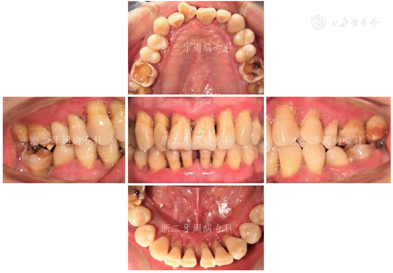

口腔卫生欠佳,软垢指数:2;牙石指数:3;全口牙龈充血红肿;平均牙周探诊深度(PD)7.0 mm,PD≥7 mm的位点占所有检查位点的63.3%(114/180),其中17颊侧远中、17舌侧远中、34舌侧远中、36颊侧近中、46舌侧近中PD深达12 mm;平均附着丧失(CAL)9.3 mm、CAL≥5 mm的位点数为98.3%(177/180);BOP(+)%:100%;37、46松动度Ⅲ度,11~17、21、22、24~27、32、34、41~43、45、47松动Ⅱ~Ⅲ度,余牙松动度Ⅰ度;36、46Ⅲ度根分叉病变。16、26、36、46牙釉质发育不Ⅲ全,11扭转,37缺失舌向倾斜,12、14~16、24、25、41、42咬合时出现异常动度,31、41可见1.5 mm左右牙间隙(图1,图2)。牙髓活力测定:17、34牙髓活力正常,36、37、46"40"无反应。